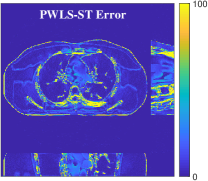

Fig.Β 5 shows the reconstructions and the corresponding error (magnitudes) images (shown for the central axial, sagittal, and coronal planes) for FDK, PWLS-EP, and PWLS-ULTRA () with the patch-based weights. Compared to FDK and PWLS-EP, PWLS-ULTRA significantly improves image quality by reducing noise and preserving structural details (see zoom-ins). Fig.Β 6 shows the RMSE for each axial slice in the PWLS-EP and PWLS-ULTRA (with the weights ) reconstructions. PWLS-ULTRA clearly provides large improvements in RMSE for many slices, with greater improvements near the central slice.

Section IV.E and Table III of [60] compared the performance of various methods for low-dose cone-beam (3D) CT reconstruction, for the XCAT phantom volume. Fig.Β 13 shows the reconstructions and the corresponding error (magnitudes) images (shown for the central axial, sagittal, and coronal planes) at for FDK, PWLS-EP, PWLS-ST (with ), and PWLS-ULTRA () with patch-based weights . PWLS-ULTRA provides better reconstructions and reconstruction errors compared to the conventional FDK and the non-adaptive PWLS-EP. PWLS-ULTRA also outperforms the proposed PWLS-ST scheme, and provides sharper reconstructions of image edges (see zoom-ins).